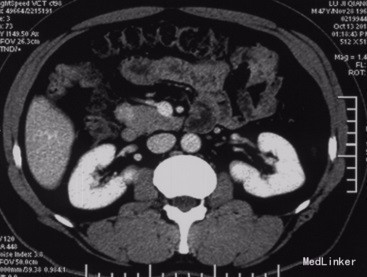

查体:神清,腹软,未及包块,无压痛及反跳痛,神经系统检查未见异常 辅查:外院头颅CT平扫:腔隙性脑梗;胰腺CT平扫:胰头、十二指肠降部稍低密度影,肝内多发小囊肿;上腹部增强CT:胰腺低密度影,考虑良性;肝内多发小囊肿。 入院检查:血、尿、粪常规、肝肾功能、电解质、凝血功能正常;AFP、CEA、CA19-9、CA125、CA15-3、CA72-4均正常;胰岛素78.33mIU/L,C肽 4.91ug/L。腹腔动脉DSA:胰头区富血供肿瘤; 胰腺增强MRI:1、胰头部富血供病变,考虑胰岛素瘤可能性大;2、肝内多发小囊肿。